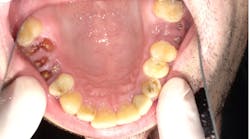

Mandibular arch occlusal view. Extensive interproximal decay on Nos. 18, 19, 30, 31. Crowns recommended on Nos. 18, 19, 30, 31. Image is prior to root canal treatment on Nos. 19 and 30 due to decay into nerve space.

No. 11 had an existing large fractured filling with a post present; a crown was needed for support as it was for No. 12. For the remaining posterior teeth, he had generalized Class-V decay. The mandibular arch was not in much better shape, with generalized Class-V decay on all posterior teeth as evidenced in intraoral images. Teeth Nos. 19, 30, and 31 exhibited decay into the nerve of the teeth and were abscessed. All were planned for root canals, build-ups, and crowns to restore function and eliminate the infections.